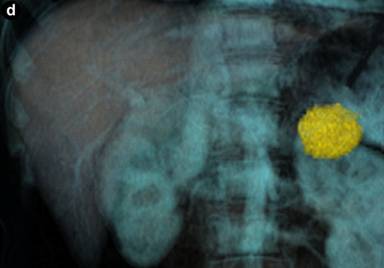

For measurement of the cyst diameter and volume, commercially available software (CT Oncology; Siemens Medical Solutions) was used on an image-processing workstation (Leonardo Workstation, syngo® 2008A MultiModality Workplace (VE26A) platform; Siemens Healthcare, Erlangen, Germany). Two independent investigators (H.C. and P.R.) with one and two years of experience using the software, respectively, performed the measurement on pancreatic parenchymal phase images. Pancreatic parenchymal phase was selected due to the superior conspicuity of the lesions in this phase. The application of this software in the volumetric measurement of abdominal masses has been described previously [13, 18]. The graphic user interface is divided into 4 screens: axial, coronal, sagittal and 3D views. Once the investigator identifies the pancreatic mass by drawing an approximate line across it, the software selects the entire lesion. This is achieved by three-dimensional reasoning by the software to remove neighboring normal pancreatic tissue, hence, generating a volume of interest around the drawn line and extends the segmentation on the basis of histogram analysis within the generated volume on interest (Figure 2). The selections can be edited by the investigator in x, y, and z planes, if necessary.

Figure 2. Coronal (a.), axial (b.), sagittal (c.) and three dimensional (d.) CT images of a histopathologically proven pancreatic tail mucinous cystic neoplasm in a 39-year-old man. Despite a dilated pancreatic duct no connection was visualized on endoscopic ultrasound with the cyst. Borders of cyst are marked with yellow line by the software. CT volumetry (22.3 mL) and an elongation value (0.67) for the cyst were automatically generated by the software once the measurement was finalized by the observer. Pancreatic head cyst was not segmented because of apparent connection with the pancreatic duct that was dilated. Also, note that the patient was a male with mucinous cystic neoplasm, an extremely rare occurrence. |